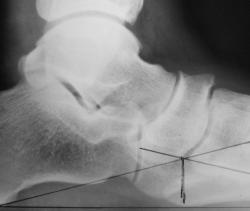

Пациент направлен из военкомата с целью определения продольного плоскостопия и стадии деформирующего артроза в суставах среднего отдела стоп.

Валентин Львович! Мне видится продольное плоскостопие 2-й степени с явлениями артроза 2-й стадии. Ладьевидная кость деформирована за счет артроза в таранно-ладьевидном и ладьевидно-клиновидном суставах. Суставные щели неарвномерно сущены более чем на 50%. Выраженный субхондральный склероз. Краевые остеофиты 2 и более мм. На мой взгляд пациент "В"- ограниченно годен.

Плоскостопие обеиз стоп 2 степени. Атроз суставов средней стопы, в виде деформирующего артроза ТЛС, ЛКС обеих стоп, справа-2 стадии, слева-1 стадии.(По данным военно-медицинской экспертизы категория В-негоден к военной службе в мирное время)

В презентации не указан возраст, копыта выглядят на 50 и старше, редко встретишь такой артрозище у молодых людей призывного возраста. И захождение ладьи в тыльную сторону вполне наглядное.

1. Это фотокопии с рентгенограмм, которые были "расчерчены" согласно методики Богданова, т.е. расчерчены рутинно.

2 ст. уплощения продольного внутреннего свода стопы, т.е. 2 ст. продольного плоскостопия, 2 стадия деф. артроза в суставах среднего отдела обеих стоп, хотя вторую в ладьевидно-клиновидных суставах можно оспорить, но это, по всей видимости, не имеет принципиального значения, так как в таранно-ладьевидных - 2 стадия.